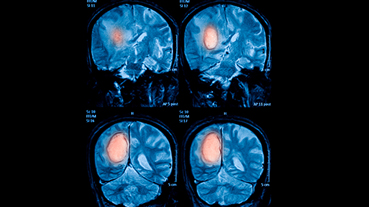

Innovative technologies and alternatives to traditional treatments are transforming the diagnosis and management of neurological conditions. In 2025, NewYork-Presbyterian physicians and surgeons from Columbia and Weill Cornell Medicine used sonication and convection-enhanced delivery to penetrate the blood-brain barrier, validated an adjunctive treatment for subdural hematoma, broadened access to spine surgery, advanced experimental therapies for neurodegenerative diseases, and more. Our specialists have been steadfast in reshaping the fields of neurology and neurosurgery in the pursuit of better patient outcomes and enhanced quality of care.

From cutting-edge research to compassionate patient practice, neurologists and neurosurgeons from Columbia and Weill Cornell Medicine are at the forefront of developing and applying the most advanced approaches to treat debilitating conditions affecting the brain and spine. With a broad range of focus on neurodegenerative and neurovascular disorders to malignant tumors, our innovative and advanced care is leading to new treatment options and enabling patients to achieve the best possible outcomes.